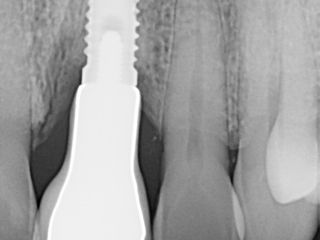

Fully Guided Implants with Screw Retained Prosthetic

This is a wonderful case of a patient who had failing bridges for years. The upper teeth had been failing and the patient had experienced moderate bone resorption (bone shrinkage due to early loss of teeth).Read Case Study